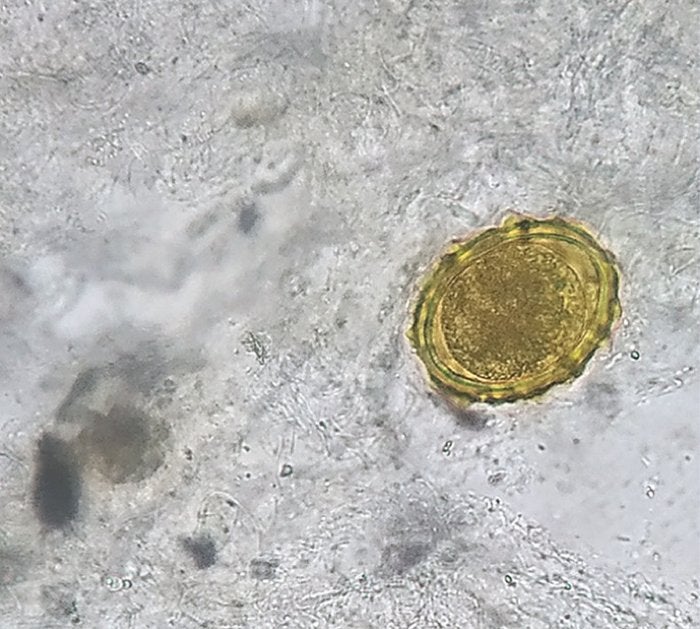

Los doctores buscaron a través de las heces del paciente restos de parásitos, encontrando que contenían huevos del gusano Ascaris lumbricoides, un tipo de parásito intestinal. De hecho, se trata de uno de los gusanos parásitos humanos más comunes en India.

Se estima que entre 800 y 1.200 millones de personas tienen A. lumbricoides en el tracto intestinal, según los Centros para el Control y la Prevención de Enfermedades (CDC). Hablamos de unos gusanos que pueden llegar a crecer hasta 35 centímetros de largo.